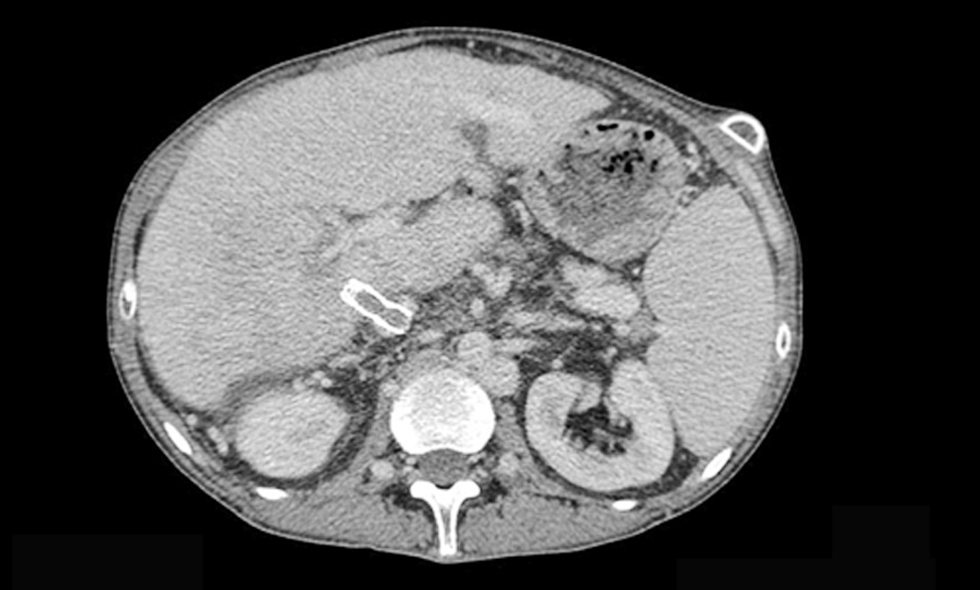

Our patient received continue theraphy with dabigratan etexilat (Pradaxa) 9 month and she performed CT scan every 3 month. In june 2018 CT scan evaluation described moderate ascities due to DIPS thrombosis (figs. 2, 3, 4).

Figure 4 - CT scan 1.5 mm portal - Direct Intrahepatic Portocaval Shunt thrombosis (June 2018)